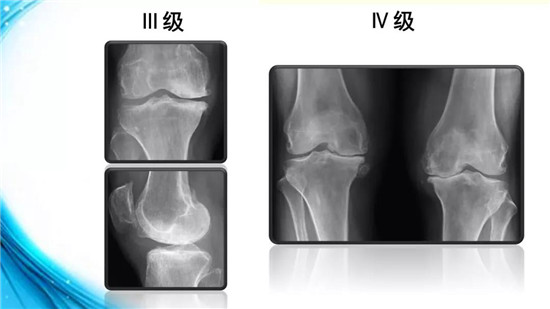

下面,我们来了解一下膝骨性关节炎的分级、分型与分期。根据X线所示,可对膝骨性关节炎进行分级。

Ⅲ级关节间隙变窄较明确,有中等量骨赘,软骨下骨骨质轻度硬化,范围小。Ⅳ级关节间隙明显变窄,有大量骨赘,软骨下骨骨质硬化极为明显,关节肥大及明显畸形。